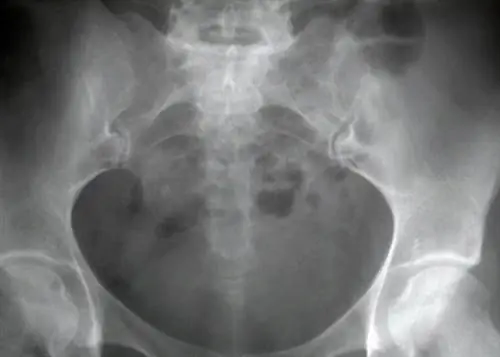

• Потеря костной массы/остеопороз - Потеря костной массы является наиболее опасным компонентом триады, так как более слабые кости могут привести к остеопении, а затем к остеопорозу, вызывающему стрессовые переломы и травмы. Стрессовые переломы и переломы костей часто проявляются в бедрах и позвоночнике спортсменов.

В другом исследовании, опубликованном в Journal of American College He alth, изучалась минеральная плотность костей элитных бегунов на выносливость. Исследователи обнаружили, что у 34,2% исследованных спортсменов была низкая минеральная плотность костей в поясничном отделе позвоночника, а остеопороз присутствовал у 33% выборки. Другие аспекты триады, в том числе менструальная дисфункция, нарушение питания и низкая минеральная плотность костей, присутствовали у 15,9% исследованных спортсменов.